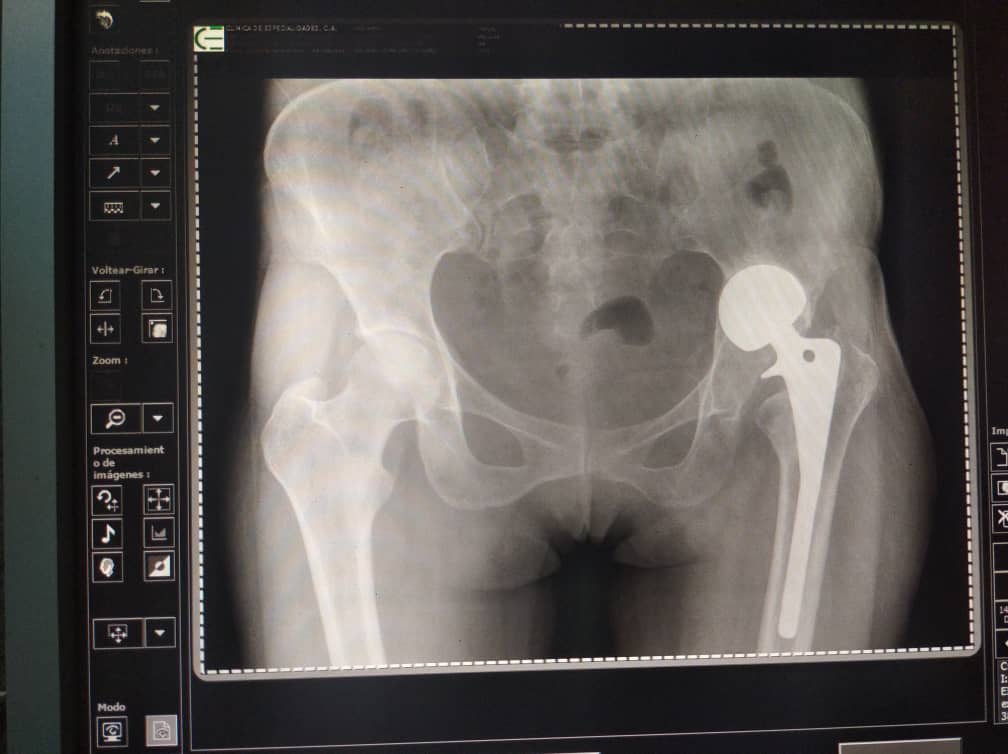

Para ese entonces, me operaron y colocaron una prótesis incorrecta en la cadera, que con el paso del tiempo se ha vencido y me está provocando severas lesiones en el área, lo cuál me causa dolores de fuerte intensidad y me impide caminar.

Los médicos me han diagnosticado signos de protusión acetabular lo cual amerita nueva intervencion quirúrgica, para el recambio de endoprótesis de cadera izquierda cementada, que deben realizarme lo más pronto posible, debido a que con el paso de los días los huesos se siguen dañando y hasta corro el riezgo de sufrir daños irreparables.